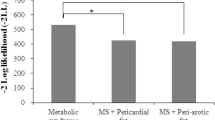

Compared with the control group, the study group had a higher left ventricular eccentricity ratio (LVER) (0.80 ± 0.13 vs. 0.72 ± 0.11 g/ml, P = 0.002), higher left ventricular global peak wall thickness (GPWT) (11.8 [9.27, 13.4] vs. 10.3 [9.27, 11.99] g/ml, P = 0.03), and higher LVM (114 ± 29.6 vs. 93.3 ± 18.7 g, P = 0.001), but there was no significant difference between the two groups after correcting for body surface area (BSA) (48.9 ± 12.0 vs. 44.3 ± 7.55 g, P = 0.053). The left ventricle global longitudinal strain (LVGLS) of the study group was lower than that of the control group (− 13.31% ± − 4.04% vs. − 15.22% ± − 2.36%, P = 0.016). The pericardial adipose tissue volume (PATV) of the study group was higher than that of the control group (116 ± 41.6 vs. 78.7 ± 20.6 ml, P < 0.001). The myocardial proton density fat fraction (M-PDFF) and hepatic proton density fat fraction (H-PDFF) of the study group were higher than those of the control group (2.93 ± 0.78 vs. 2.30 ± 0.71, P = 0.001; 20.6% ± 7.81% vs. 12.7% ± 8.49%, P < 0.001), and the abdominal subcutaneous fat area (ASFA) of the study group was higher than that of the control group (293 ± 84.4 vs. 237 ± 90.4 ml, P = 0.012) (Table 2).

The AVFA had a moderate positive correlation with LVER, LVM, LVGLS, PATV, and M-PDFF (ρ = 0.39–0.59, P < 0.001) (Figs. 3, 4). After adjusting for clinical and laboratory indicators in Models 2–4, the correlation between the AVFA and cardiac MRI indicators slightly weakened. After adding other cardiac MRI indicators to Model 5, the AVFA still had a slight correlation with LVER and LVGLS, but it was not correlated with left ventricular mass (LVM), PATV and M-PDFF. There was a moderate positive correlation between the AVFA and H-PDFF (ρ = 0.49, P < 0.001) (Fig. 4), and the correlation slightly weakened after adjustment for all variables but was still statistically significant. There is a slight correlation between the AVFA and ASFA (ρ = 0.289, P < 0.016), which still existed after correction for Models 2 and 3. However, the correlation disappeared after adding MRI indicators in Models 4 and 5 (Table 3). We found that BSA was correlated with LVER (r = 0.29, P < 0.05) but not with LVM (Additional file 1). There was no difference in systolic and diastolic function between the right ventricle and most left ventricles between the two groups.

Pearson correlation analysis between abdominal visceral fat area and cardiac MRI results. A-D shows the correlation between AVFA and LVER, LVGLS, LVM and GPWT respectively. The statistics at the top of the graph include the P value of indexation, the ρ value of correlation, the 95% confidence interval and the number of statistical samples. LVER left ventricle eccentricity ratio, LVM left ventricular mass, LVGLS left ventricular global radial strain, GPWT global peak wall thickness

Pearson correlation analysis between cardiac and abdominal MRI results. A-C shows the correlation between AVFA and PATV, M-PDFF, H-PDFF respectively, D shows the correlation between H-PDFF and hepatic T1 values. The statistics at the top of the graph include the P value of indexation, the ρ value of correlation, the 95% confidence interval and the number of statistical samples. AVFA abdominal visceral fat area, PATV pericardiac adipose tissue volume, M-PDFF myocardial proton density fat fraction, H-PDFF hepatic proton density fat fraction